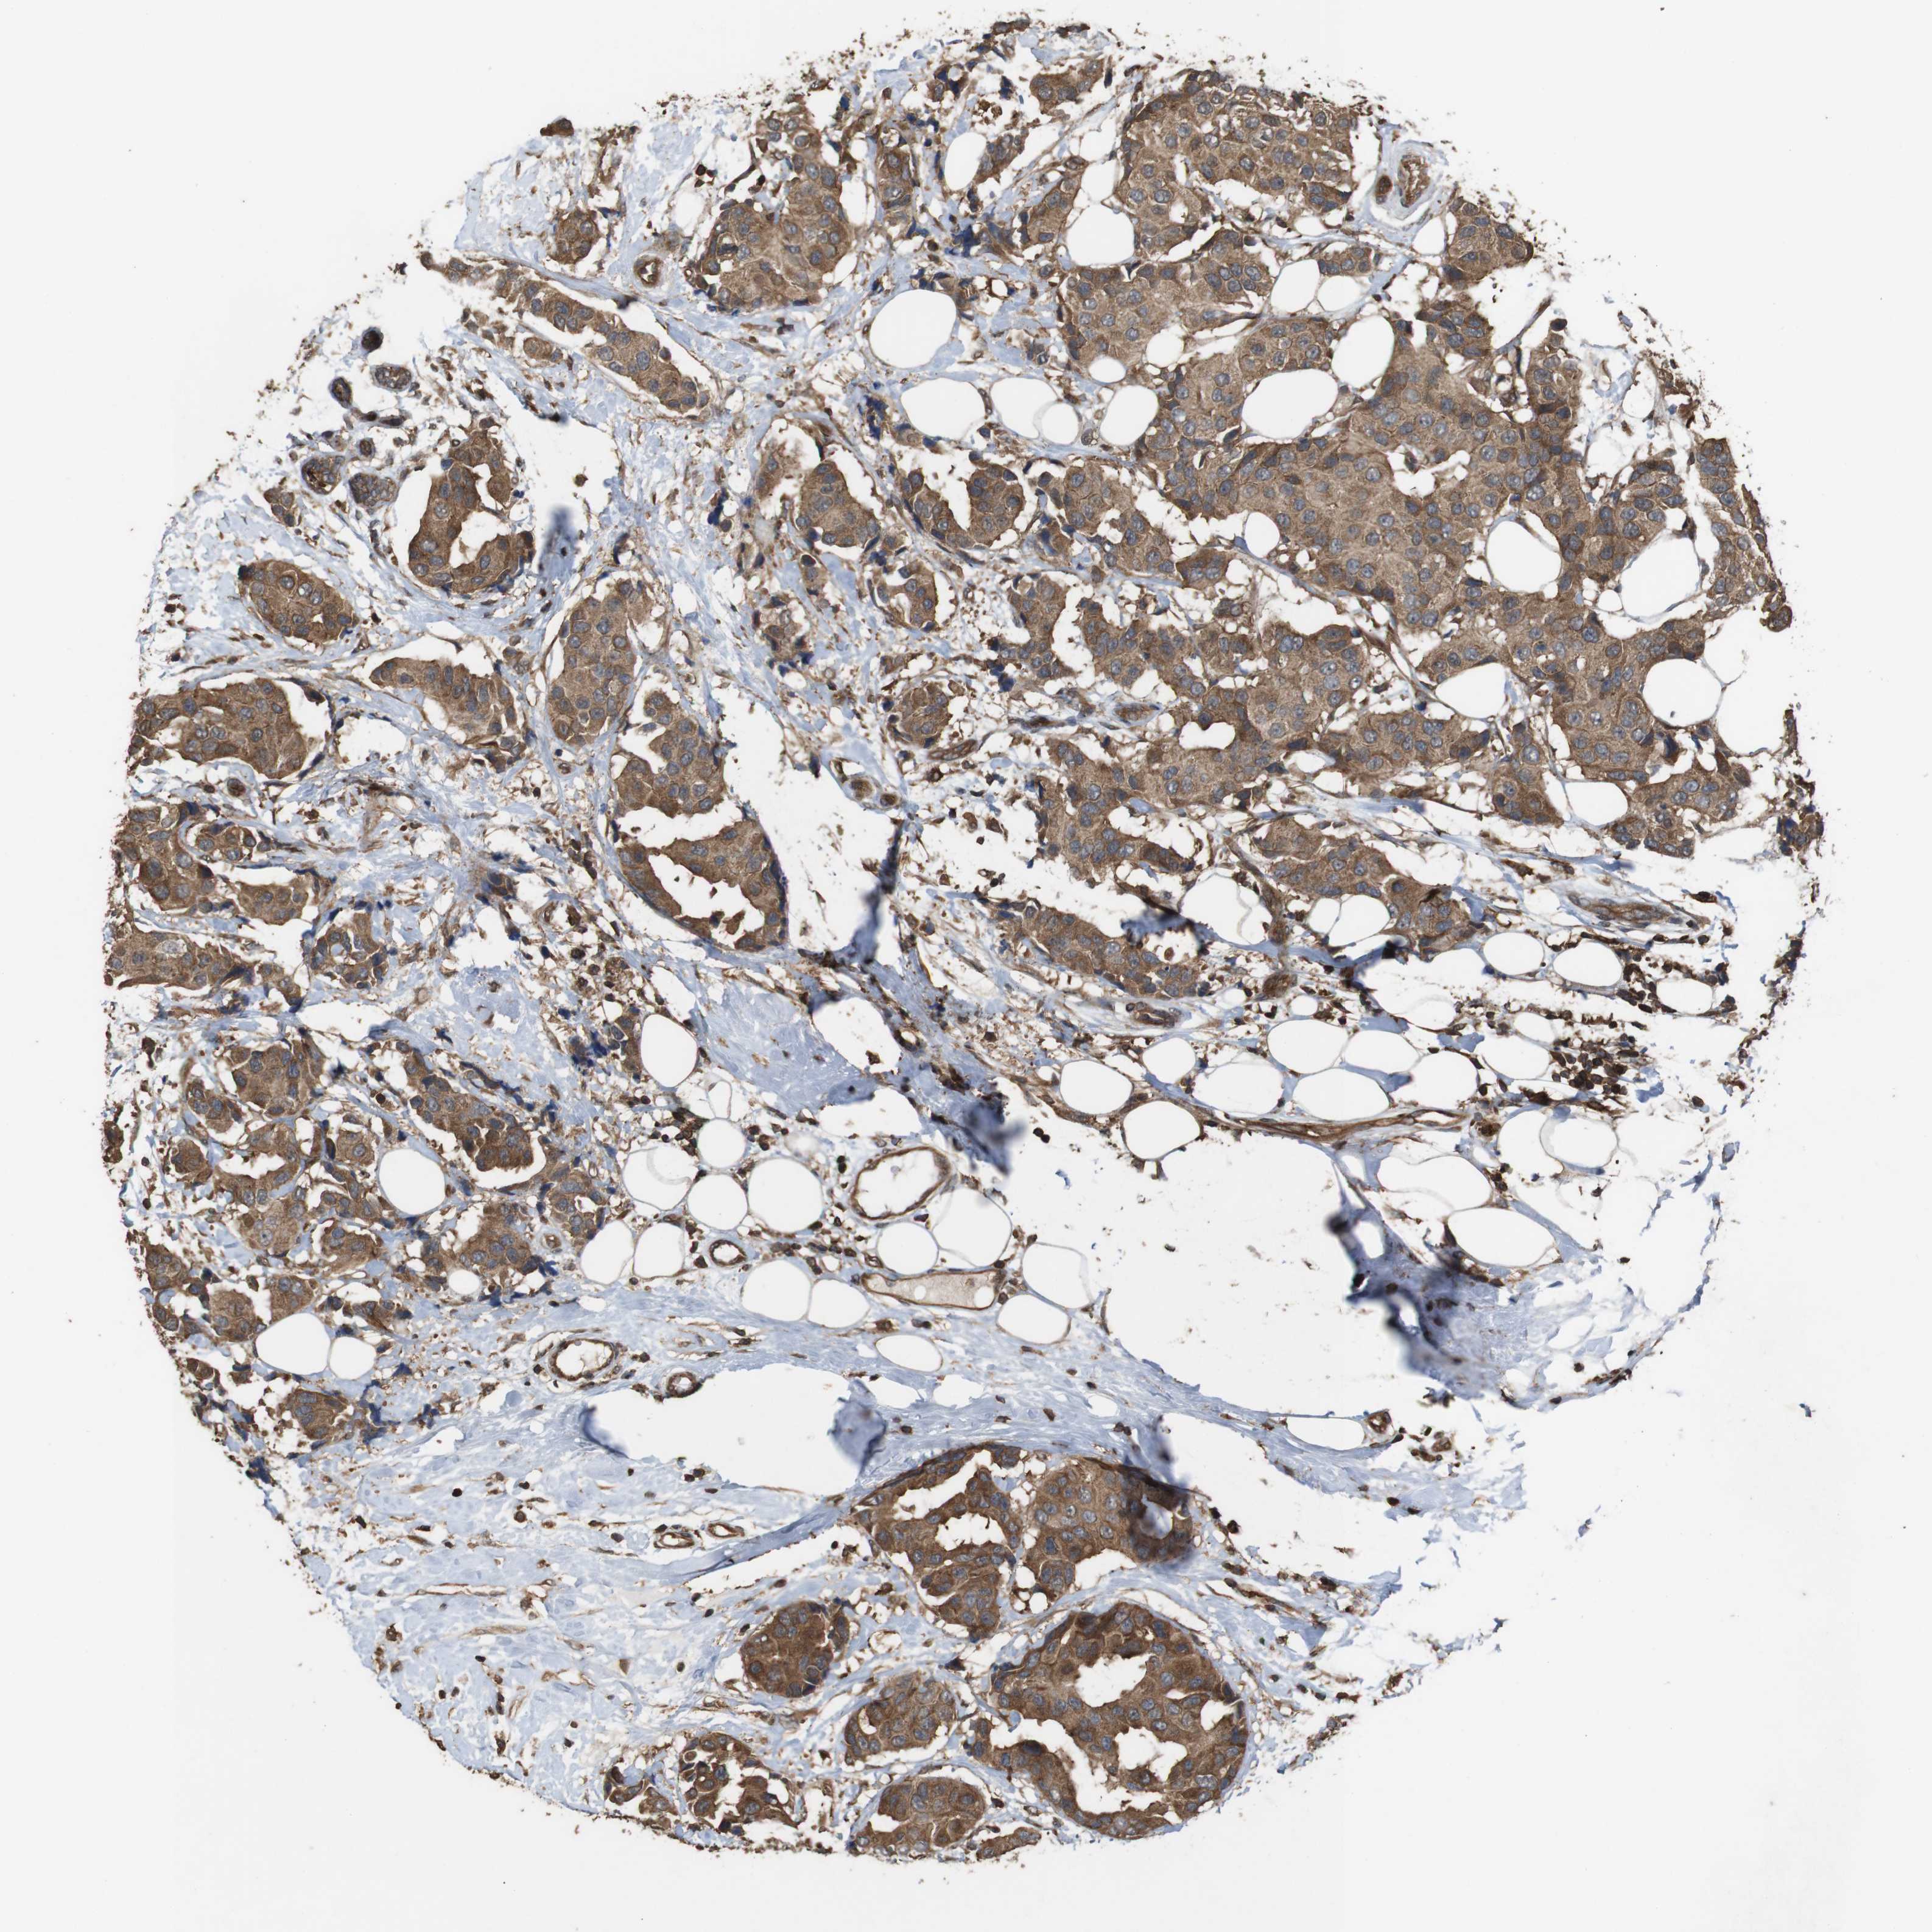

CANCER BREAST CANCER Show tissue menu

BRCA TCGA BRCA VALIDATION PROTEIN EXPRESSION